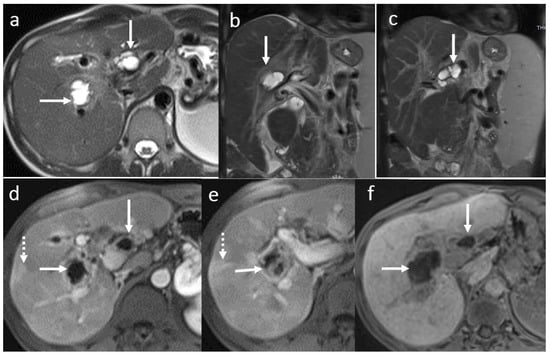

3.4. Biliary Anastomotic Stricture

3.5. Biloma and Bile Leaks

3.6. Secondary Cholangitis

3.7. BT Lithiasis